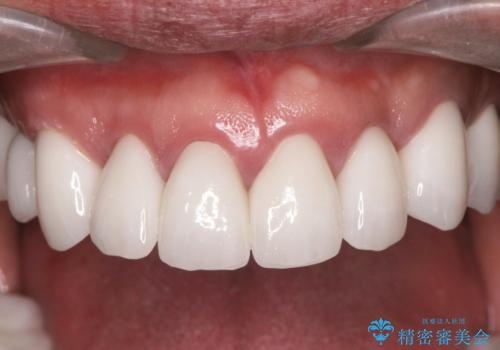

歯周外科を行い歯と歯槽骨・歯肉の関係を是正することで歯ぐきの状態を改善し、将来に亘り安定した歯周環境の維持を期待できるセラミック治療を実践します。

- 95.7万円(ジルコニアクラウン×6・仮歯×6・歯周外科)費用は治療当時の料金となります

歯ぐきが腫れたままの状態だと、違和感が生じるとともに常に炎症が存在する環境となってしまうので非常に好ましくない口腔内環境です。